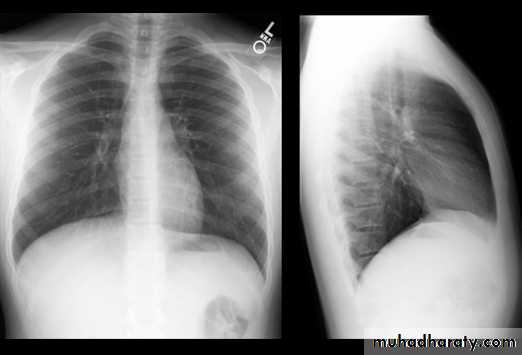

CXR of adult male PA and lateral views, it shows :Normal both lung fields ,Central cardiac shadow, Central trachea, central mediastinum, No boney lesions, no soft tissue abnormalitiesnormal radiologic anatomy of the chest Look carefully on both diaphragmatic cruse costo & cardio phrenic angles. Useful in detection of pleural effusion